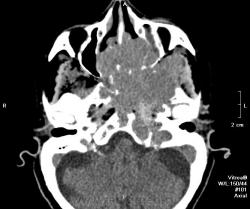

Краниофарингеома? Есть ли данные контрастирования?

Нет, контрастирования не делали. Бабушку отпустили домой, сказали, что опухоль неоперабельная. Вряд ли это краниофарингиома. Скорее это опухоль из основной пазухи или из решеток. У нас она прошла как опухоль основания черепа. Увы!